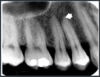

What is the labelled arrow?

Root canal

Labelled arrow?

Root canal

Are these root canals visible in the last 2 mm?

Frequently not visible in the last 2 mm.